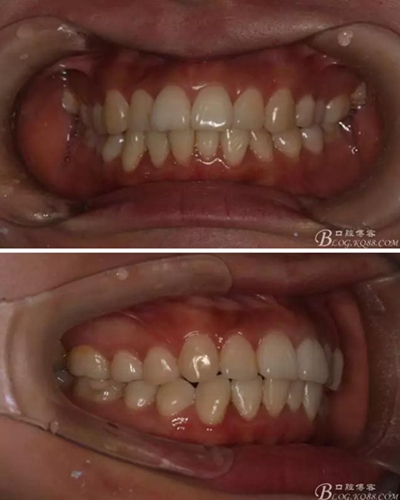

患者,女,主訴:牙齒不齊。

如圖,該病例為簡(jiǎn)單排齊病例,但77鎖合是矯治中的關(guān)鍵所在,你會(huì)怎么處理?

該病例主要為17、27頰側(cè)位同時(shí)伴有伸長(zhǎng),當(dāng)然種植支抗可以解決,但還有簡(jiǎn)單實(shí)用的辦法嗎?如圖,在橫腭桿遠(yuǎn)中延伸出牽引鉤,位置盡量遠(yuǎn)離合平面,7粘舌側(cè)扣,牽引力的方向?yàn)閴旱图吧嘞?,下圖為兩個(gè)月的效果,17已到位,27還未到位。